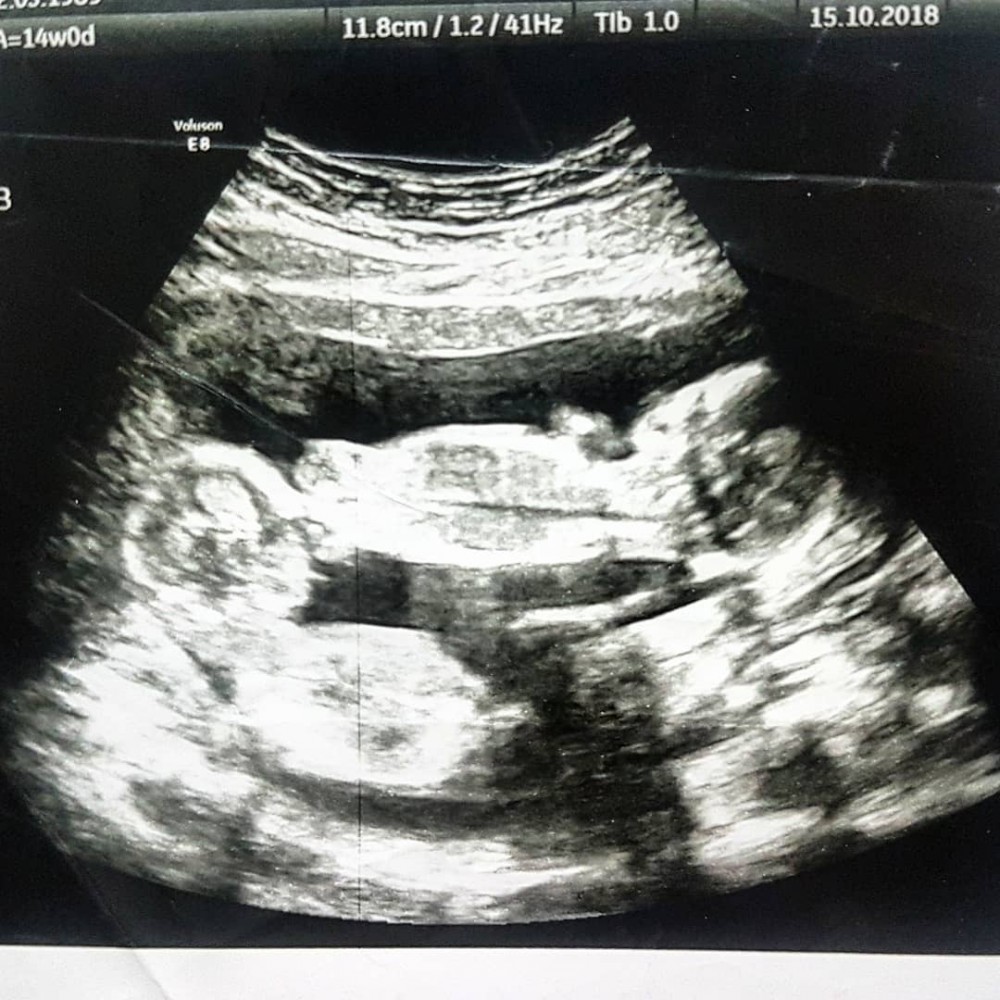

雙胞胎 機率

» 同卵 雙胞胎 機率 (97) 사진

同卵 雙胞胎 機率 (97) 사진